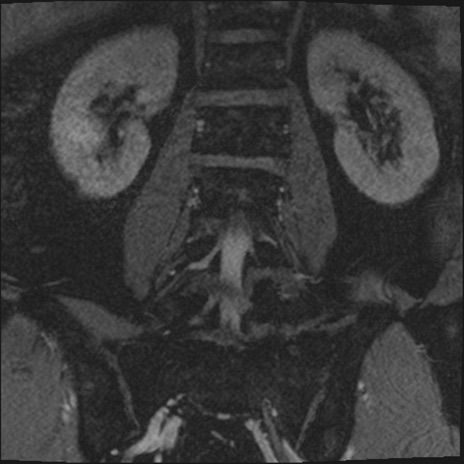

【整形】TIPS症例2 腰椎MRI 3D(冠状断像)

【症例】70歳代男性

【主訴】左下肢痛

【現病歴】2週間前くらいから腰痛、左下肢痛あり。左臀部から大腿、下腿外側のしびれが常時ある。歩行とともに同部位の痛みあり。

【身体所見】Lasegue70-/60+、Bragard-/±、PTR ±/±、ATR -/-、IP 5/5、TA 5/4、TS 5/5、EHL 右第1足趾なし/3、FHL 5/5、hypersthesia(-)、足背動脈触知良好

異常所見と診断は?